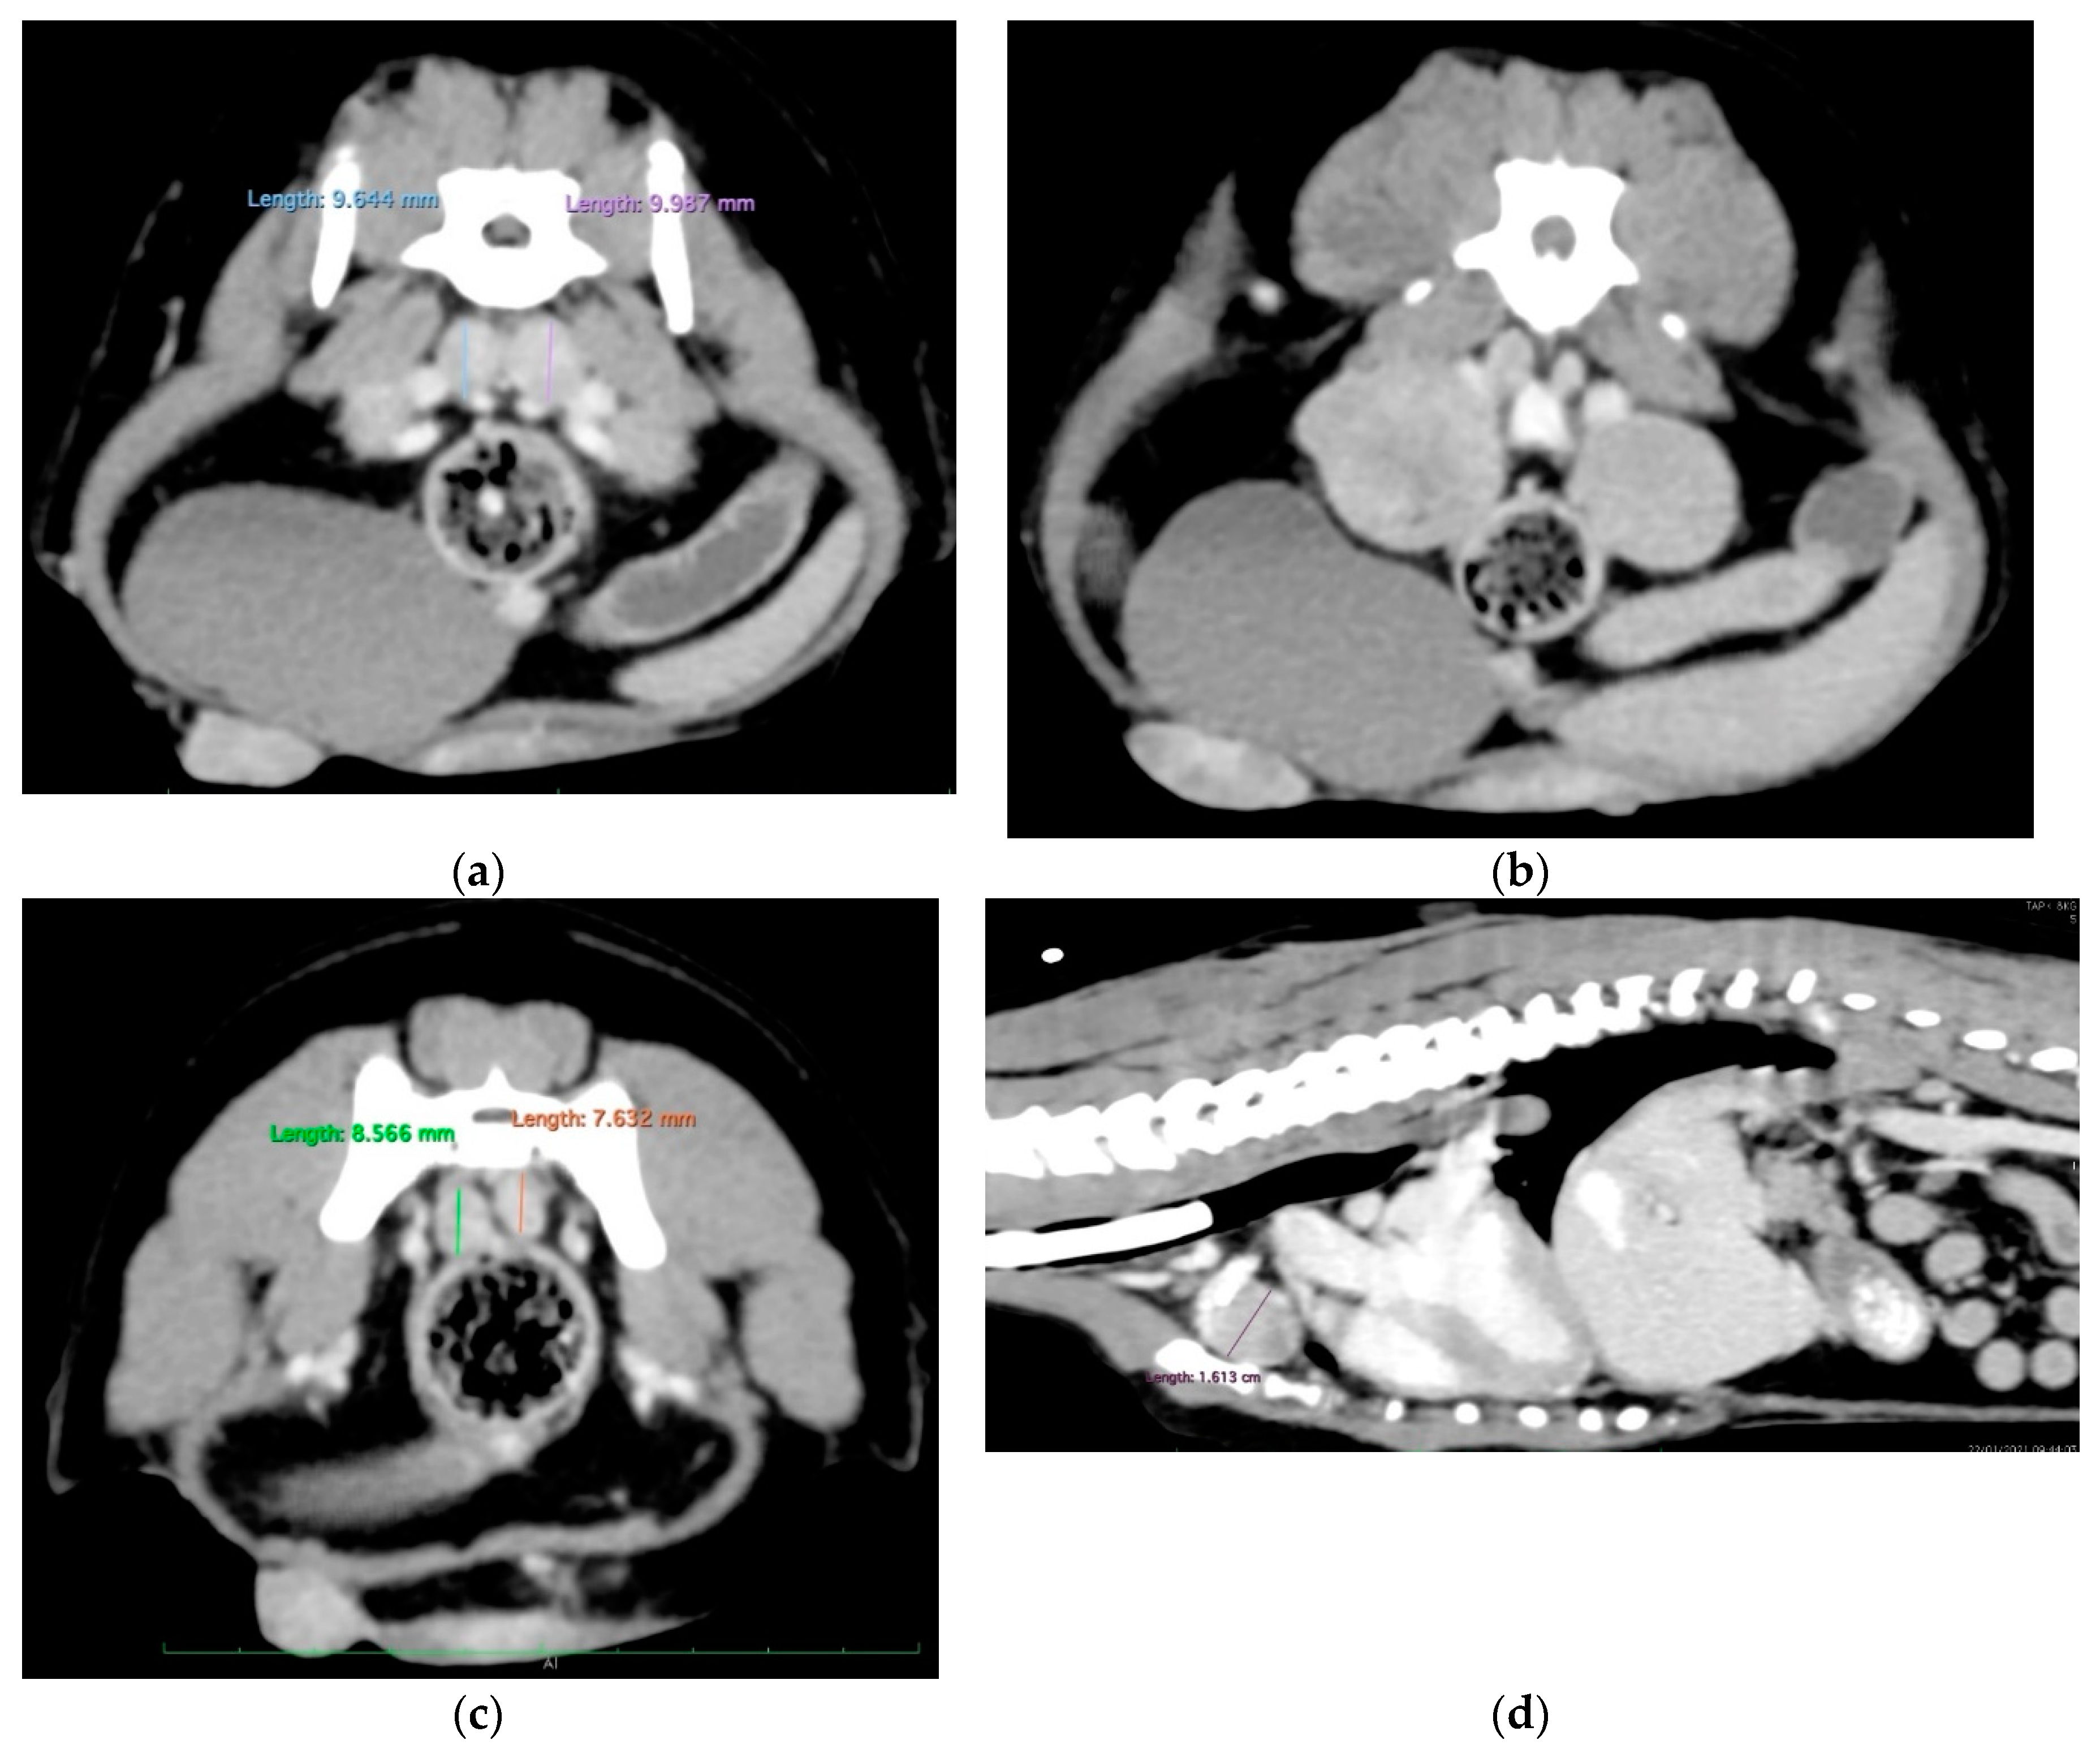

| 21/09/01 | flaccid tail, evolving into posterior paresis within 24 hours spinal metastases (CT examination) and death on 21/09/22 |